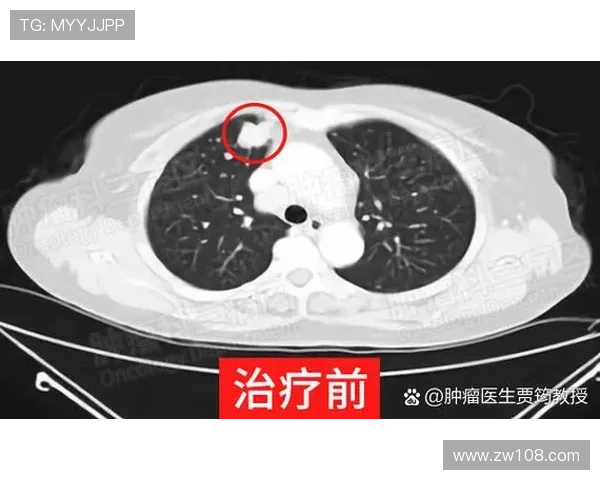

在受伤初期,医疗团队曾多次进行影像学检查与康复评估。经过数次专家会诊,确认黄威的伤势需要通过手术方式进行彻底修复。医生们认为,保守治疗已无法达到稳定和强度的要求,而现代微创技术可以最大限度地保留关节功能,为其未来复出打下基础。

手术方案的制定过程严谨而科学。医疗团队在多次会诊后,最终确定了微创修复结合重建的综合方案。该方案既能有效修复损伤部位,又能缩短康复周期。医生们通过3D影像技术,对黄威膝关节的受损结构进行了精准建模,从而确保手术切入点与修复角度的科学性。